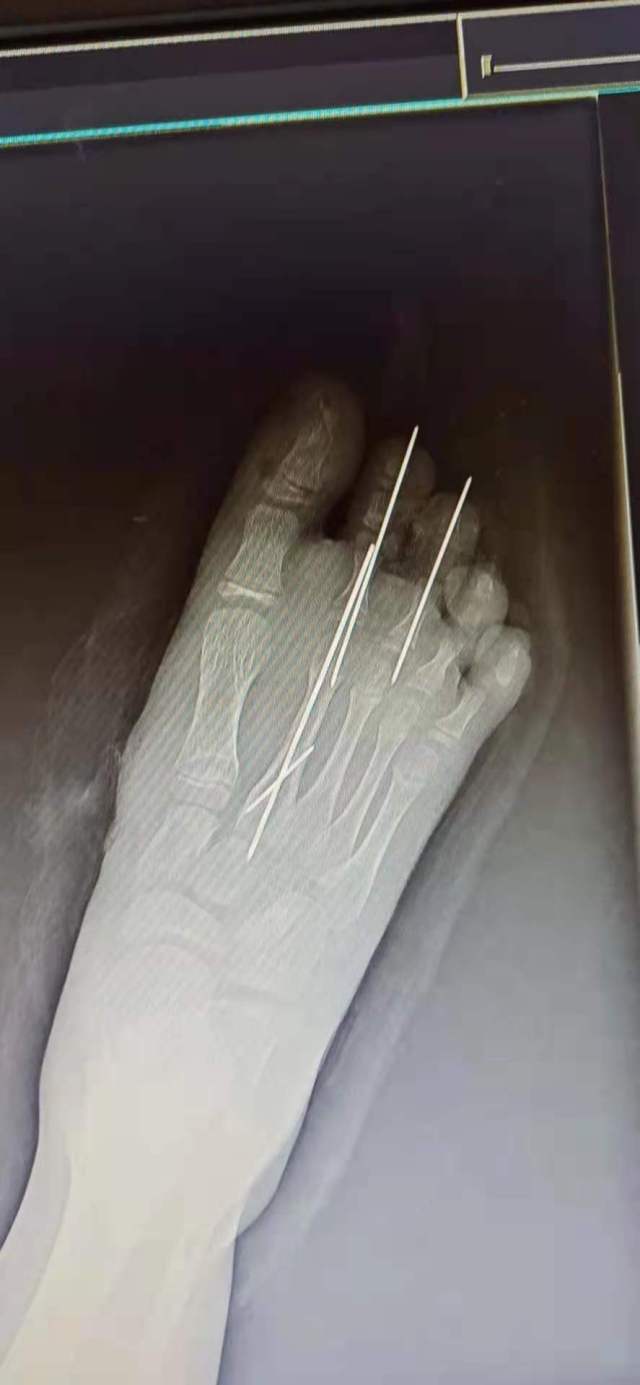

“右脚第一第二足趾离断,右足背大片皮肤软组织缺损,多发趾骨跖骨骨折。”浙江省人民医院手外科和修复重建外科主治医师范奔接诊后,根据当地医院检测报告及现场检查,迅速作出诊断。

在科主任杨晓东指导下,范奔等手外科团队急诊为患儿行右第一第二足趾再植及骨折内固定术,辅以石膏外固定。由于患儿离断足趾挤压严重,术中从左足取健康血管替代了右足受压毁损的血管,经数小时紧张手术,离断的足趾终于接回去了。 “在显微镜下,用比头发丝还细得多的缝线,精确吻合血管神经,接起一个指头就需要几小时。”杨晓东主任介绍说。